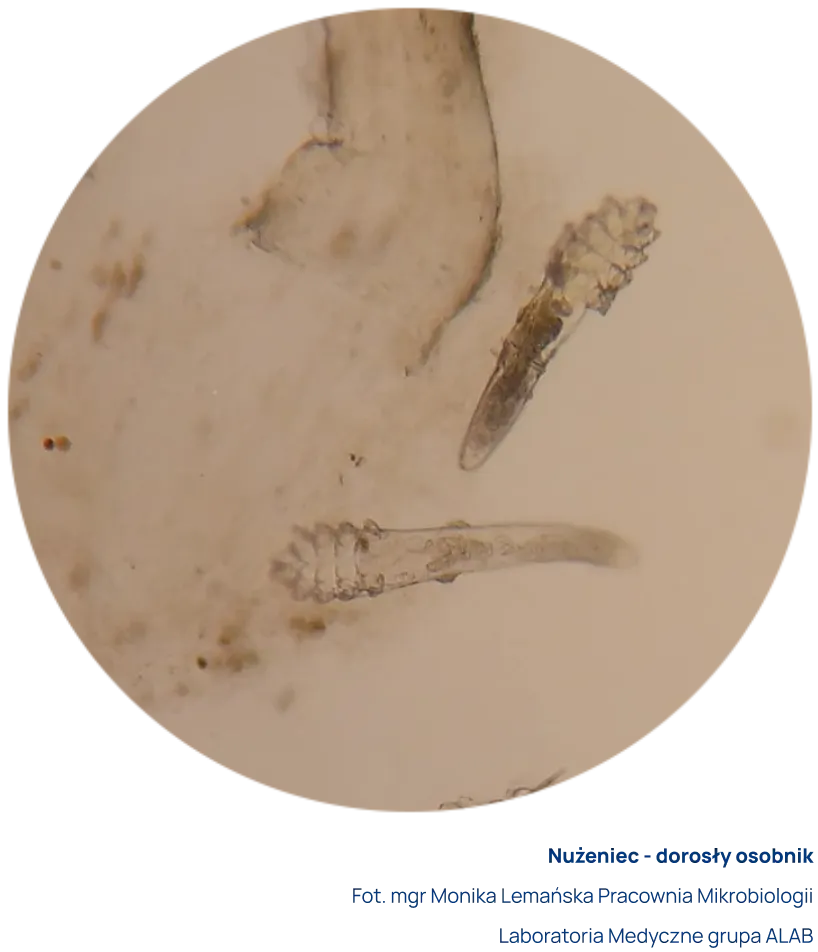

Do badania pobiera się za pomocą pincety rzęsy z obu oczu. Rzęsy umieszcza się w specjalnym płynie. Preparat mikroskopowy ogląda się bezpośrednio po pobraniu z użyciem mikroskopu świetlnego w powiększeniu x20. Dopuszczalny jest transport z Punktu Pobrań do Laboratorium w jałowym suchym pojemniku.

Do badania pobiera się zeskrobiny ze zmian skórnych bezpośrednio na szkiełko mikroskopowe. Zalewa specjalnym płynem i ogląda przy użyciu mikroskopu świetlnego w powiększeniu x20. W przypadkach podejrzenia demodekozy skórnej zaleca się wykonywanie badania bezpośrednio w Laboratorium wykonującym to badanie.

Za dodatni wynik uznaje się obecność w preparacie postaci dorosłych, larwalnych i/lub jaj nużeńca z jednoczesnym występowaniem objawów klinicznych